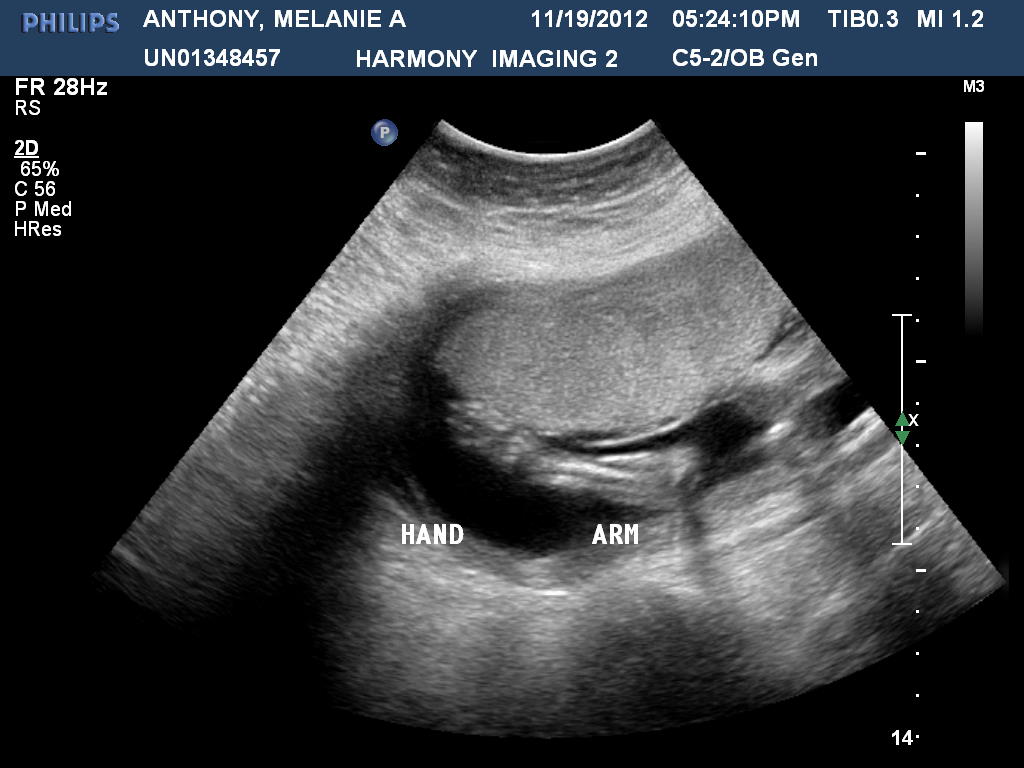

I know I said before I was gonna try to post each week about how things are going, but nothing has really changed until our appointment we had today November 19th was our second Dr. Appointment which went pretty good.. Things just keep changing for the good..We came into this appointment wanted to talk to the Dr. about maybe doing an Ultrasound or when she planned on doing one.. So Dr. asked me if I had any questions I started asking her about meds I can take for my cold, what kind of lotion I can use to put on my belly to try to stay away from stretch marks, and then I asked her the question.. Lol.. I asked her how she thought I was growing, if she thought I was bigger then I should be at how far along I thought I was and she looked at me and said I was fine, then I told her that my coworkers think I’m having twins, so she decided to touch my belly to feel for my uterus and that’s when she told me that she thought maybe they were right, that my uterus was bigger then it should be, she said it should be under my belly button and it’s just right above it.. I was like Uh-oh and began telling her that I was a twin and asked her if I had a chance and she asked if I was fraternal or identical.. I guess franternal twins have a better chance or something, so I was getting a little worried again.. she tried looking for the baby’s heart and see if there was another one, took her a little bit, but she finally found it a little lower then she thought ( it was 150 at the clinic) and was like yeah we need to schedule an ultrasound, I was like that was my next question.. So she said maybe tonight, but it’s kinda late so maybe tomorrow we told her tomorrow afternoon would work better for us. She was going out of town tomorrow afternoon so she was hoping we could get in soon. I told her I could probably wait until after Thanksgiving if I needed to and she’s like No you can’t because she knew that I was nervous and scared. Lol.. so she went to tell the nurse then a few mins later the nurse comes back in and was like so we got you an appointment for tonight in like an hour, so here is what you need to do.. You need to drink 40 oz of water and not go to the bathroom. I was like seriously I can’t do that I can’t not pee and especially when I’m drinking water.. she just kinda laughed at me.. So after wards we got a bottle of water and went and walked around Kohls for a little bit to waste some time as I’m drinking this water.. I was doing ok.. then we left and pulled in and I told Gil I can’t do this I have to go to the bathroom soooo bad.. So this lady asks us if we have an appointment and I give her the paper and told her I have an uncomfortable bladder, so she told me I might be able to go a little, but not a lot, and I was like I’ll be ok.. as we are talking to this other lady filling out paperwork answering questions I just couldn’t take it any longer and was like can I just go a little I can’t do this!!.. LOL… so she calls the tech to see what I can do and she tells her that she is on her way to come get me.. She finally comes to get me and then lays me on the bed and tells me I can put my legs up if it’s comfortable and I said no I have to leave them down, so she starts scanning for the baby and taking pictures, we then find out that we are having ONE baby and not twins.. sorry for those of you who were hoping for us to have twins maybe next time… LOL… Then she tells me I can go a little..then I lay back down and she’s scanning again Baby’s heart rate was 135 this time, and we told her what it was earlier and she said it was fine.. she then asks us do you want me to tell you guys what you’re having If I can figure it out.. I’m like WHAT how far along am I?? she’s like I’m not sure, but your around 19-20 weeks, I was like OMG really… She tells us that I’m already half way done, so crazy to think about.. so she starts scanning and taking pictures then tells me I can go again until I’m done and I was like Yay happy bladder!! Never been more excited to go to the bathroom.. Lol.. so anyway after wards she starts scanning me again and taking more pictures.. During all this scanning and taking pictures that baby is moving all over and kicking and moving it’s arms.. We were unable to find out the sex of the baby cuz of course it’s legs were crossed and it wouldn’t uncross it’s legs and she was already having problems trying to get pictures of the baby cuz it was moving all around.. Once we were done she gave us a cd, with 4 pictures on it, I’m kinda disappointed on the pictures she gave us because it was 2 face pictures, an arm picture and legs.. we didn’t get the profile picture or anything else. . Kinda bummed about that and that the baby wasn’t cooperating so we couldn’t find out what it was, but oh well guess that’s the least of my worries and it will be a surprise.. she said we won’t do another ultra sound unless the radiologist didn’t like any of the pictures she got or if something was wrong with me.. so we’ll just have to plan accordingly since we don’t know.. Kinda ruins some plans I had, but I’ll figure it out.. All that matter is Baby is ok and it is so that’s good.. So she told us at the end that I am 19 weeks and 5 days along, not 13.. Lol.. and that baby weighs 11 oz.. and new due date will be April 10th, not May 22nd!!.. As I was talking with my Sister and told her the due date she was like maybe you’ll have a March baby and I was like oh yeah maybe I will.. ( cuz I wanted a March baby sometime cuz that’s the only month out of the year that Gil’s family doesn’t have a Birthday.. ) so Maybe I will that would be cool. .But we’ll see.. I’m thinking about maybe looking into seeing how much the 3D ultrasounds are, kinda wanna get one of those done, but it all depends on how much it costs.. Might look into it just for the fun of it that would be my next chance to see what we are having.. Lol.. we will see though.. I’m not even sure I’m able to express how I’m feeling.. I’m very happy that Baby is doing well from what she could see.. I guess I’m just shocked that I’m further along then we thought, I am just surprised I didn’t know I was pregnant before I found out she was saying well you can have your period sometimes when you’re pregnant well that’s obviously what happened so weird to think about it.. I’m a little more nervous now, just cuz I know it’s coming more quickly and worried that we might not be able to come back to Wisconsin after Christmas like we planned guess we will play it by ear and see what my Dr. says… I will post the Baby’s ultrasound pictures below that we got, but as for more belly pics well I’m gonna now have to back track and figure out just really how far along I was in the pictures.. Lol.. so I’ll post those later.. ;-)